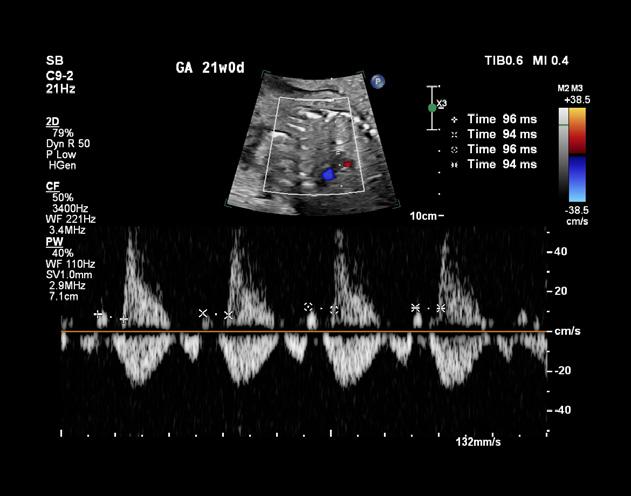

À la naissance, le nouveau-né est souvent bien coloré, rose, et ne présente pas de gêne particulière. Cependant, la présence d’un souffle cardiaque systolique, perçu dès l’auscultation en salle d’accouchement, attire l’attention. Un souffle d’apparition précoce nécessite une échocardiographie d’urgence.

Dans sa forme habituelle, la tétralogie de Fallot est bien supportée à la naissance et ne demande pas de traitement immédiat. Il est toutefois utile d’hospitaliser le nouveau-né en unité de réanimation pédiatrique pour une surveillance attentive. La cyanose, signe classique de la malformation, apparaît généralement plusieurs semaines après la naissance, d’abord lors d’efforts ou de colères. Au repos, elle reste modérée et difficile à détecter sans observation experte. La cyanose s’accentue progressivement, accompagnée de fatigue, gênant les acquisitions motrices de l’enfant.

Grand enfant et adulte

Il est rare de rencontrer une tétralogie de Fallot non opérée après l’âge de deux ans. Cela peut se produire dans des formes particulières ou dans des pays en voie de développement. Dans ces cas, le tableau clinique présente une cyanose plus ou moins profonde, accompagnée de fatigue et de dyspnée, limitant les possibilités d’effort en raison d’un manque d’oxygène et non d’une insuffisance cardiaque.

Étiologie, âge d’apparition et évolution

La tétralogie de Fallot est la conséquence d’une anomalie de cloisonnement du tronc artériel.

Anomalie chromosomique

Une microdélétion 22q11 serait présente dans près du quart des cas et serait à rechercher avant toute anomalie conotroncale. Ce type d’anomalie chromosomique est également associé au syndrome de Di George qui comporte fréquemment une atteinte cardiaque de type de tétralogie de Fallot.

Les autres anomalies chromosomiques fréquemment retrouvées sont le syndrome de Down ou trisomie 21, la trisomie 13, la trisomie 18 et le syndrome des yeux de chat.

La tétralogie de Fallot est une malformation décrite dans plusieurs syndromes, la plupart étant génétiques : syndrome-charge, syndrome d’alcoolisme fœtal.

Elle se forme principalement au cours du deuxième mois de la vie intra-utérine. Le diagnostic peut être posé avant la naissance grâce à l’échographie fœtale, avec une détection dans 70 à 80 % des cas (jusqu’à 100 % avec un échographiste de référence). Le plus souvent, il s’agit d’une découverte de novo, sans antécédent familial particulier.

Traitements et pronostic